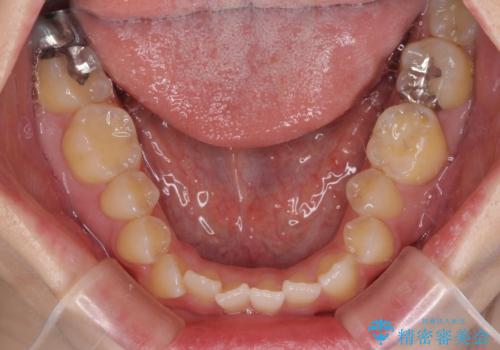

オープンバイトと前歯のデコボコをインビザライン矯正で解消

- 前歯の開咬を気にして来院された患者様です。

開咬の治療は、前歯を閉じるように動かすとともに、上下臼歯を圧下(骨内にめり込ませる)させることで進めて行きます。

インビザラインは臼歯の圧下を効果的に行えるため、インビザラインを用いて矯正治療を行うこととしました。